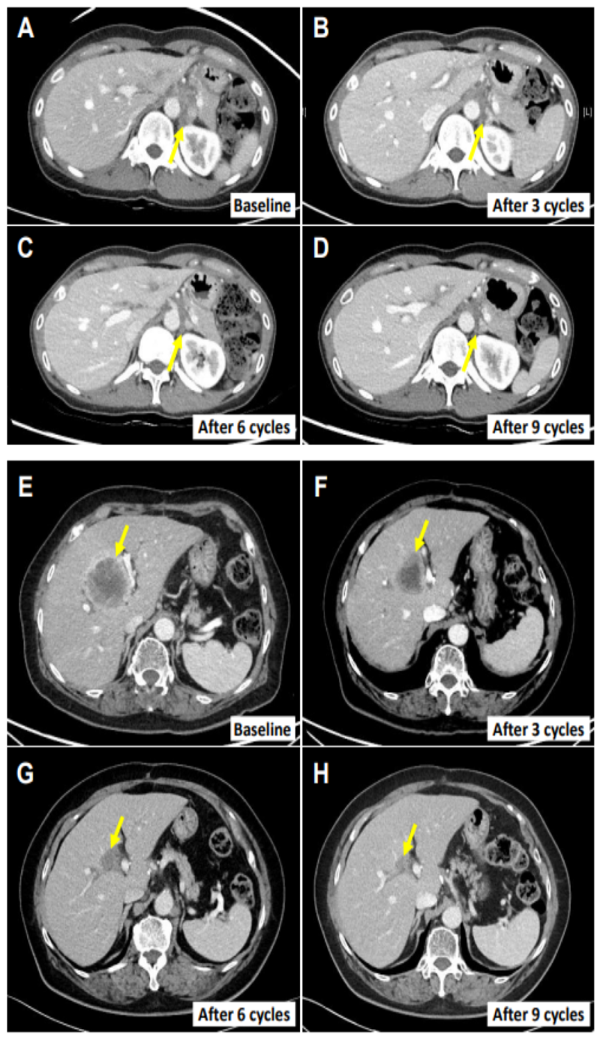

值得注意的是,患者E0107为一例40岁女性,因胆囊炎行胆囊切除术,术后病理确诊为胆囊癌合并腹膜癌。其病史中已包含使用吉西他滨、顺铂、5-氟尿嘧啶(5-FU)、伊立替康脂质体及亚叶酸等多种化疗药物的治疗经历。在采用NK细胞疗法联合帕博利珠单抗治疗后,其转移性淋巴结体积显著缩小,减小幅度高达82.3%。

图:其中2名患者的肿瘤消退影像情况